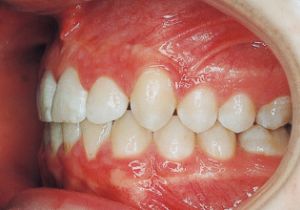

2 After Treatment 6-24-’95

Class II deep bite in mixed dentition. A significantly large overjet and a spaced arch are observed. The cephalometric X-ray shows that the anteroposterior displacement of the maxilla and mandible is not particularly large (ANB 5°), but the nasal floor is elevated anteriorly, providing evidence supporting a history of thumb sucking. The skeletal form shows a relatively slight mandibular body deficiency, but the mandibular ramus is adequately sized and appears likely to develop sufficiently. The use of headgear was planned to suppress maxillary anterior growth and achieve relative mandibular advancement. Treatment was performed without extraction, assuming continuity until the permanent dentition stage.

4 After Treatment 6-24-’95 3 years and 7 months after starting treatment